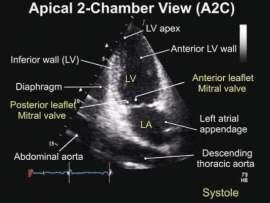

Lee masApical 2 chamber view Importance: 1)Assessment of Ischemia “RWMAs” 2)Viewing LV apical thrombus 3)Assessment of MR and its mechanism 4)Assessment of pericardial effusion 5)viewing Coronary sinus and LAA ..